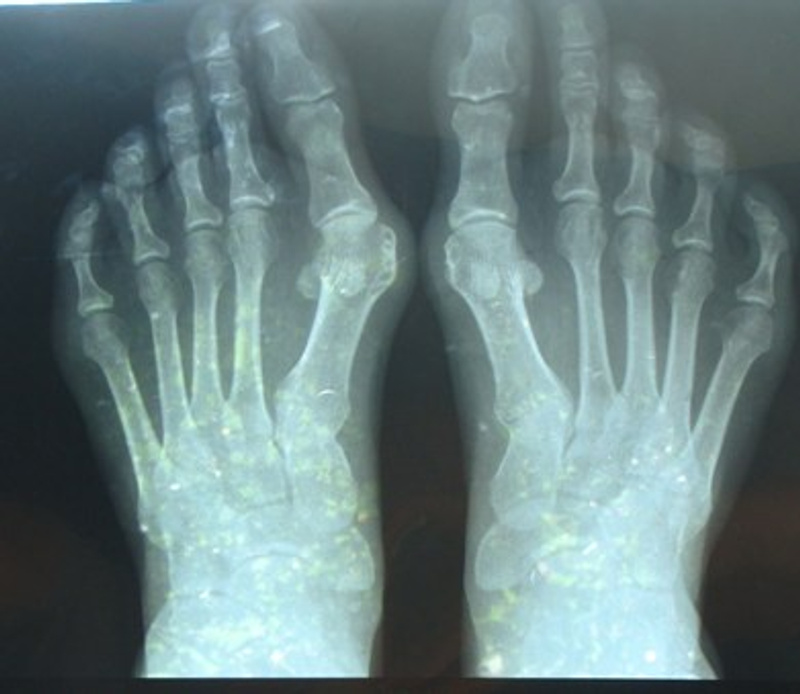

Оперировал Пахомов, хотя записывалась я у другого, они как-то все поменяли в последние дни. У меня в каждой ступне по 2 винта (скрепляют большой палец и кость в стопе) - это была остеотомия. Шрамы на мой взгляд не бросаются в глаза (может завтра сфотаю и выложу до и после). Фитнесом я занималась, с этим все нормально. Правда первую зиму после операции я лыжный сезон пропустила, хотя запрещено мне не было. Ещё мне говорили, что можно после заживления костей вытащить винты (или у кого пластины), но естественно проходить оперативное вмешательство опять я не собиралась. По поводу восстановления: недели полторы после выписки по дому я каталась на стуле с колесиками - жалела себя и не ходила:)... потом месяц ходила в спецобуви (о ней писали выше), выглядело это по дурацки, но уж точно лучше костылей с гипсом. Потом ещё месяца 3 ходила в удобной мягкой обуви на плоской подошве, вот и всё. Спрашивайте что интересует, а то у нас реально об этом мало информации.Ответ на сообщение Re: Косточки на ногах пользователя AverAnna

. Информации, действительно об этом мало, хотя проблема распространнённая и операций проводится много... Если не трудно, пожалуйста, выложите фото ДО и ПОСЛЕ, ничто так не вдохновляет на ОП, как увиденный реальный результат :D. Или можете скинуть их мне на мейл ollga-h@yandex.ru. Вообще, хотелось бы иметь с Вами какую-то связь постоянную (мейл или номнр тел.), чтобы в случае необходимомти задать вопросы. Я ходила к Пахомову месяц назад, правда, без снимка, т.к. ещё кормила грудью ребёнка, просто хотела подробнее узнать об ОП. У меня после беременности стопа совсем "разошлась" и появилась боль - неврома Мортона, может быть Вы знаете, что это такое. Так что на ОП настроена однозначно, нужно решать проблему косточек и плоскостопия, пока не стала инвалидом. Пахомов всё подробно рассказал о методике ОП и мы договорились встретиться ещё раз после того, как я закончу гр. вскармливание. Вот я его закончила, скоро пойду сделаю снимок и опять к нему. ОП буду делать в начале сентября, чтобы с НГ выйти на работу. И дочь уже немного подрастёт, папа с ней один справится :D. Но Пахомов мне сказал, что остеотомия они больше не практикуют, используют только методику с установкой пластин, на мой вопрос "почему отказались?", ответил, что при такой ОП чаще возникают рецедивы. Но я думаю, что рецедивы возможны, если не заниматься своми ногами в дальнейшем, не беречь их (я имею ввиду ортопедич. стельки, высокий каблук как можно реже).Когда-нибудь я стану лучше и мудрее, чем теперь (с)